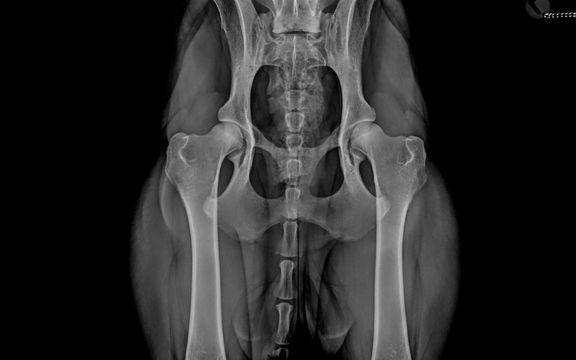

Offizielle HD, ED, OCD-Untersuchung

Im Rahmen der Zuchtuntersuchung für die Rasse Deutschlanghaar werden bei uns offizielle HD-, ED- und OCD- Röntgenaufnahmen angefertigt ...